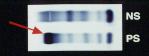

次の症例は67才、男性です。3年ほど前から糖尿病と診断され、その際、血中からM蛋白が検出されるも関連検査所見などから良性M蛋白血症(MGUS)として経過観察を行っていましたが、平成10年3月、脳内出血のため緊急入院となりました。その際の主な検査成績をスライドに示します。セ・ア膜電気泳動による血清蛋白分画ではmidからslow-γ位に強いM蛋白帯が観察され、免疫グロブリンの定量ではIgA 4,310mg/dLと著増し、IgGは減少しておりました。 |